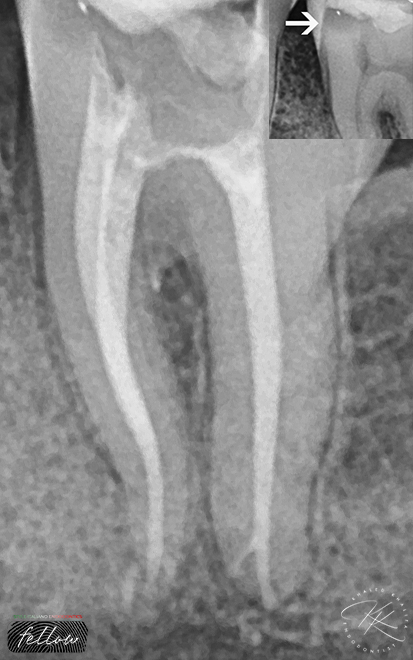

S-Shaped Roots, require different approach during cleaning and shaping.

The most important advice I can give you is using taper 4% along with Controlled Memory heat treated NITI can help ALOT.

Using OTR as well can help reducing the stresses on the file to safely navigate throughout the canal space.